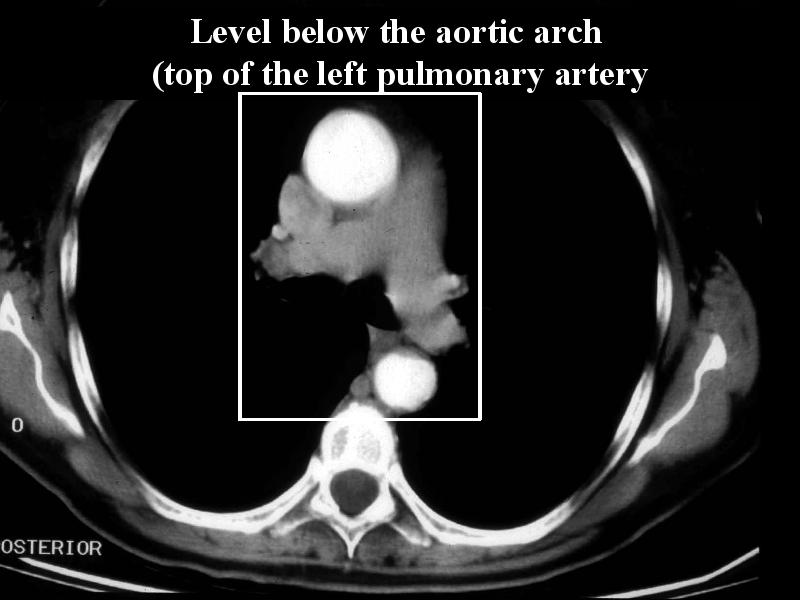

MS 156 CT 62